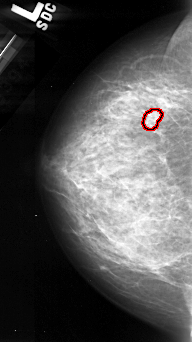

A_1097_1.LEFT_CC

LEFT_CC LINES 4441 PIXELS_PER_LINE 2491 BITS_PER_PIXEL 16 RESOLUTION 42 OVERLAY

FILE: A_1097_1.LEFT_CC.OVERLAY

TOTAL_ABNORMALITIES 1

ABNORMALITY 1

LESION_TYPE CALCIFICATION TYPE PLEOMORPHIC DISTRIBUTION CLUSTERED

ASSESSMENT 4

SUBTLETY 4

PATHOLOGY MALIGNANT

TOTAL_OUTLINES 1

BOUNDARY